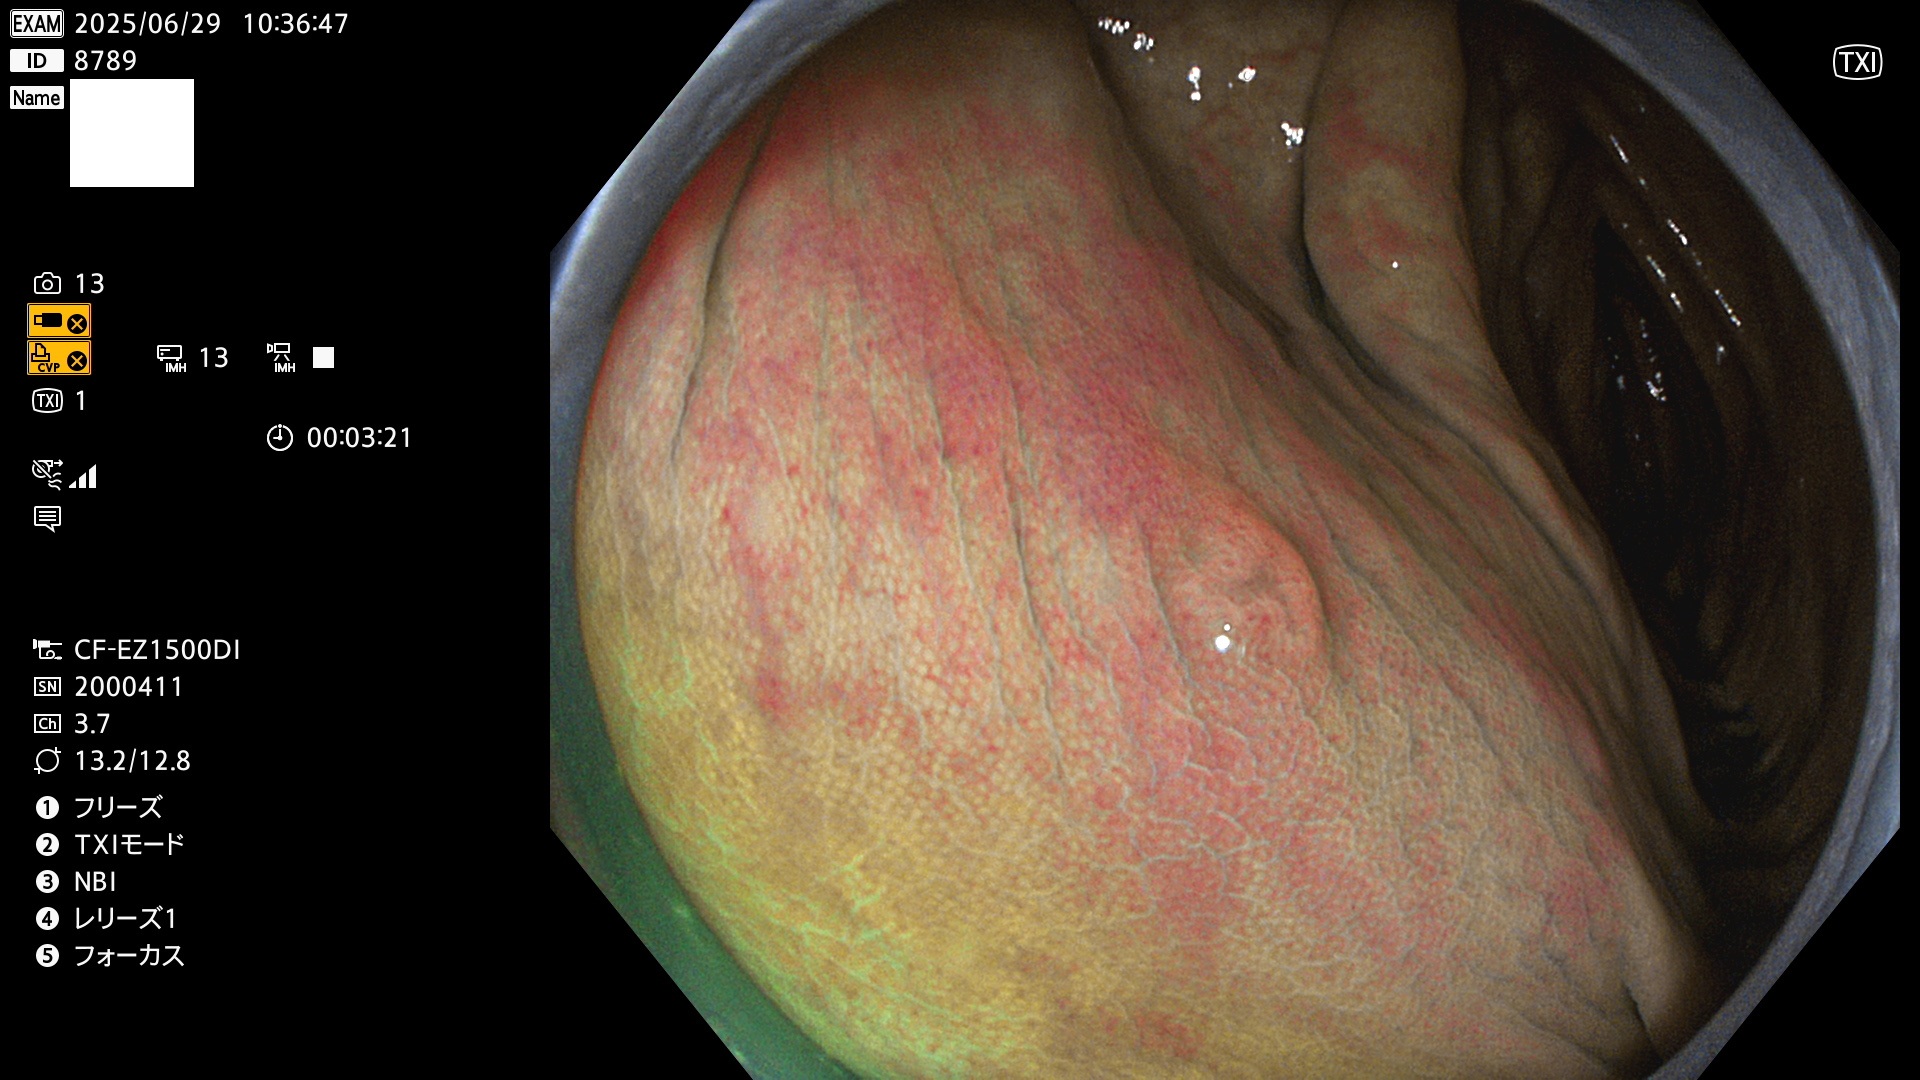

今週のUb、Uc型腺腫

完全に平坦な物をUb、陥凹している物をUcと呼びます。Ubは認識が困難で、Ucはびらん(炎症)と紛らわしいために見落とされやすく、「内視鏡後・大腸癌」の原因になります。

毎週の検査(木・金・土・日)に発見されたUb、Uc型・腺腫を、その週の日曜の夜にUPし1週間、提示します。

抽出の対象期間 2025年6月26日〜6月29日の4日間(40件の検査)7個 (7/40=18%)